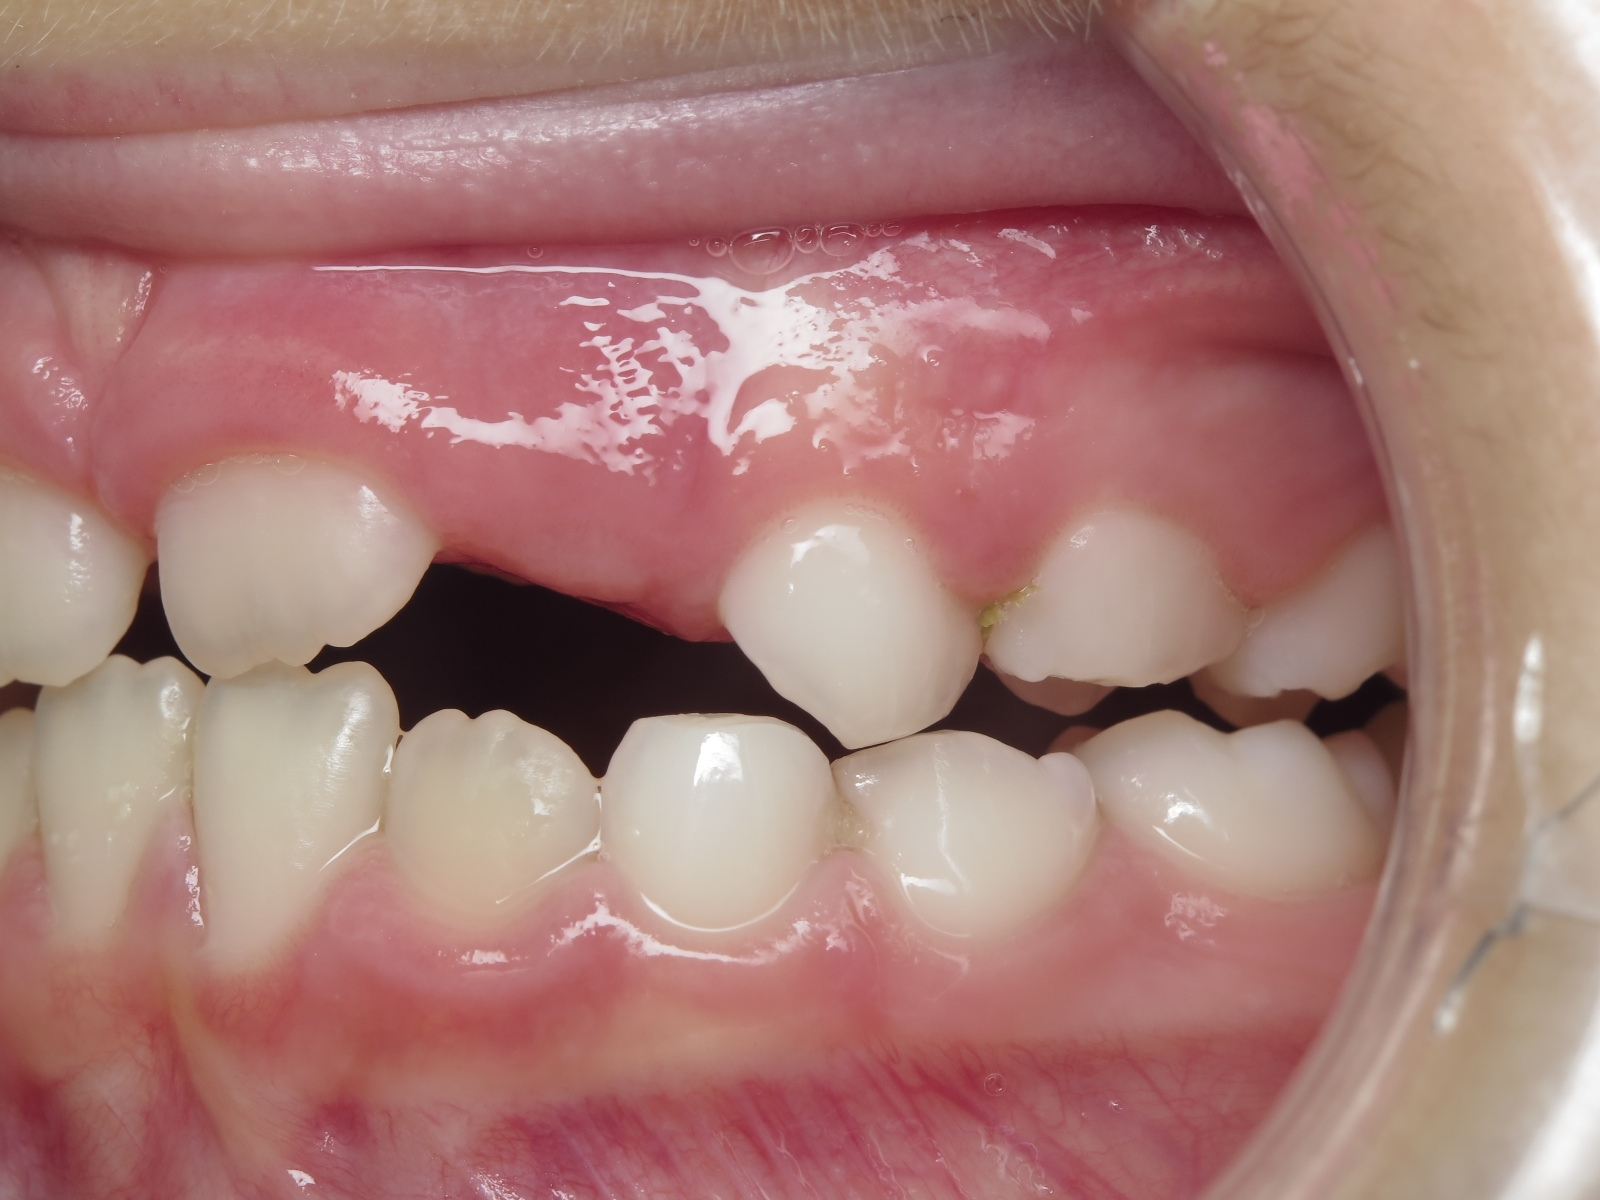

appareillage mobile pendant 22 mois

bilan début et en cours de traitement